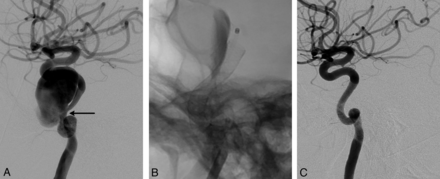

Lateral angiogram shows a giant dissecting ICA aneurysm (A). The intraoperative view demonstrates PEDs (sizes, 4 × 202 and 4.5 × 16 mm) opening to the normal size of the parent artery at the dissected segment (arrow in A) without necessitating balloon angioplasty. Note the contrast stagnation within the sac (B). Six-month control angiography (C) shows total occlusion of the aneurysm and reconstruction of the parent artery.

Left vertebral angiogram (A) demonstrates the left PCA aneurysm, which presented with left thalamic infarct (not shown). Immediate postoperative view (B) shows the single PED (2.5 × 20 mm) placed in the left PCA, resulting in contrast stasis within the sac. Control angiography (C) after 6 months confirms total occlusion of the aneurysm with the PCA preserved.